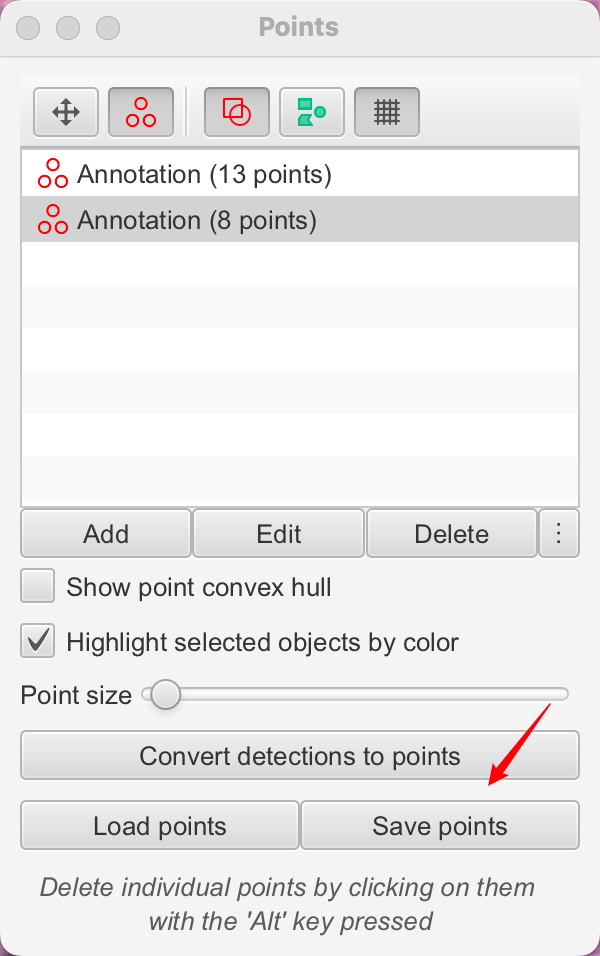

4-3:保存与导出

一旦您完成计数,您可能只需要从列表中读取点的数量。如果您像往常一样保存图像数据,点将包含在.qpdata文件中,如果需要,可以以这种方式恢复。这是如果您想在QuPath中继续处理数据时首选的保存方法。

但是,如果您希望将所有点的坐标导出以在其他地方导入,您也可以在计数面板中选择“ Save points”选项。

这将保存坐标以简单的制表符分隔格式,这可能有助于将数据导入到其他软件应用程序中。